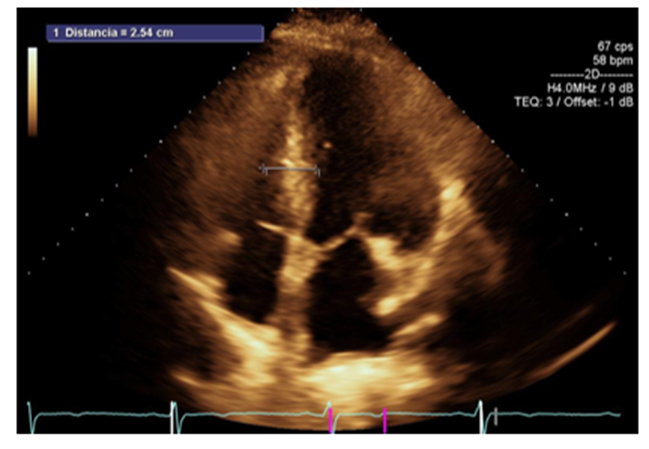

The first case, with a benign course and good prognosis, involved a 57-year-old female patient with a family history of hypertrophic heart disease, a 45-year-old sister being treated for heart failure, and healthy family members. The patient had cardiovascular risk factors characterized by a sedentary lifestyle, type 2 diabetes, and systemic arterial hypertension, both of which were at target levels with pharmacological treatment. The patient had a history of cardiovascular functional class decline for approximately 5 years. The reason for consultation was due to worsening of symptoms for approximately 6 months, upon questioning he was in NYHA functional class I, his primary physician performed a first approach with a chest x-ray and electrocardiogram where criteria for left ventricular hypertrophy and cardiomegaly grade III respectively were evident, he was referred to the cardiology of our unit where on physical examination we found the patient with rhythmic heart sounds of adequate intensity, without murmurs, with apex displaced to the anterior axillary region, a transthoracic echocardiogram was performed where non-obstructive asymmetric septal hypertrophic cardiomyopathy was documented without obstructive gradient (5mmHg), nor significant increase in it after the Valsalva maneuver, diastolic dysfunction with a restrictive pattern and increased filling pressures, the myocardium with a honeycomb image suggestive of an infiltrative pattern, the left ventricle with increased internal diameters and indexed volumes, with preserved systolic function of 61% by Simpson biplanar method. Due to family history, genetic screening was performed, finding a mutation in the tropomyosin 1 gene, variant c.841A>G;p. (Met281Val), classified as of uncertain significance, is associated with hypertrophic cardiomyopathy (OMIM: 115196), in addition to dilated cardiomyopathy and non-compact myocardium, all with a benign course, with autosomal dominant inheritance. Therefore, management was established with ACEI and Beta-blockers, with functional class monitoring, last assessment in December 2024 without functional class progression, currently without surgical criteria, continues without obstructive gradient.

Figure 1: Apical 4-chamber axis showing asymmetric septal hypertrophy